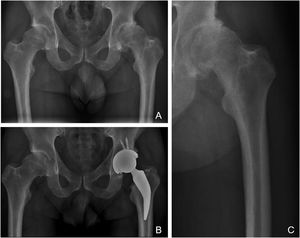

La filosofía de fijación del vástago investigado clasificado como tipo 1B de la clasificación de Kheir et al.5, tiene fijación en tres puntos en el área del calcar y cortical proximal femoral con fijación metafisaria. El cuello femoral y calcar resisten la carga y transmiten la misma a la diáfisis. La preservación a nivel del cuello aumenta la estabilidad del implante en forma rotacional y junto a la fijación metafisaria sin invasión diafisaria evitaría parte de las incongruencias que se aprecian en los fémures tipo A de la clasificación de Dorr que son más frecuentes en adultos jóvenes30. Vemos en este tipo de implantes son una solución valida a la potencial incompetencia fémur-implante cuando deben ser colocados en un fémur Dorr A, siendo que el tallo corto no invadiría el canal a nivel diafisario y sortearía la zona de conflicto, evitando así potenciales fracturas femorales o problemas en la fijación metafisaria de un tallo no cementado estándar al intentar introducirlo en un canal demasiado fino. Como se puede observar en la figura 3, en donde a pesar de no preservar hueso en el cuello femoral como sugiere la técnica quirúrgica y la filosofía del implante, la indicación de implantación de un tallo corto se vería beneficiada por su potencial revisión con un tallo de fijación metáfiso-diafisaria, al no invadir la zona diafisaria (fig. 3).

Radiografías de un paciente masculino de 38 años con diagnóstico de artrosis avanzada de su cadera izquierda y fue sometido a RTC. A) Radiografía AP preoperatoria donde se observa una falta de cobertura de ambas caderas, con desgaste severo de su cadera izquierda y corticales femorales gruesas que podrían corresponder a la clasificación «A» de Dorr. B) Radiografía AP postoperatoria inmediata donde se puede observar un RTC izquierdo con restauración de la biomecánica de su cadera, nótese que el vástago corto no invade el canal femoral a nivel diafisaria, evitando conflictos de incompetencia fémur-implante. C) Radiografía focalizada del fémur izquierdo preoperatorio donde se observa con más detalle el potencial conflicto para colocar un vástago estándar no cementado en un fémur Dorr A.